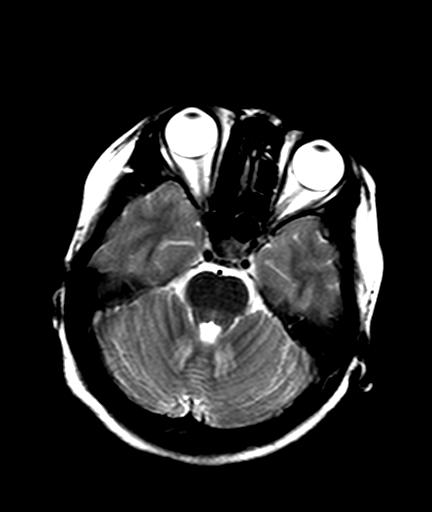

标题: MRI2408:脑内病变

发热、头痛伴精神异常1周

较对称性脑白质异常信号,深部白质t2明显低信号(铁质沉积过多?)

考虑脑白质病变,请结合临床病史及实验室检查进一步分析。